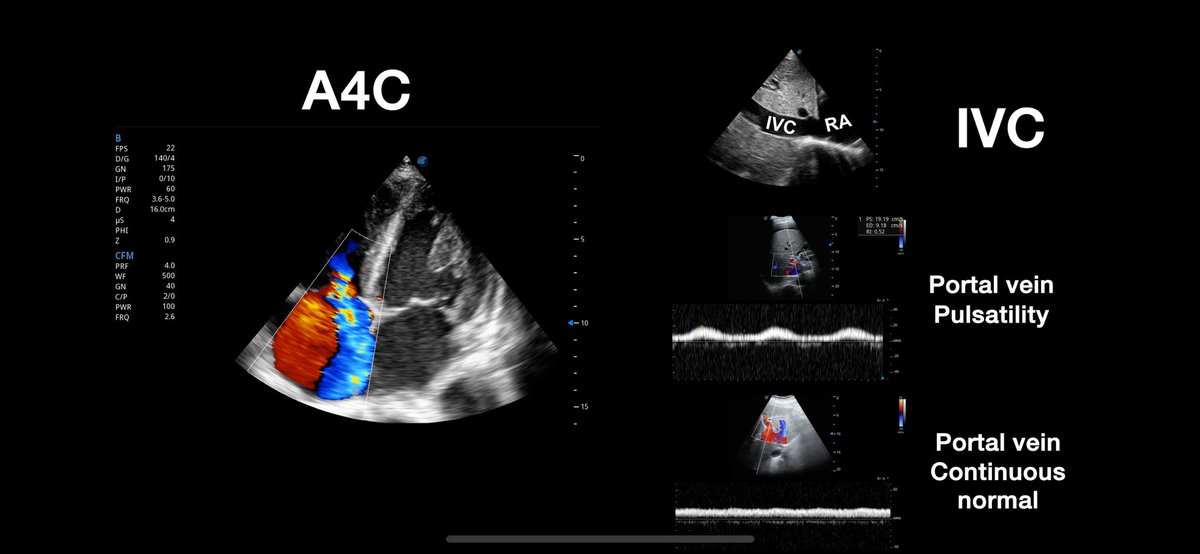

You are a great expert in this topic. Always learning from you. La porta aporta

@Tubulocentric

Gregorio Romero-González